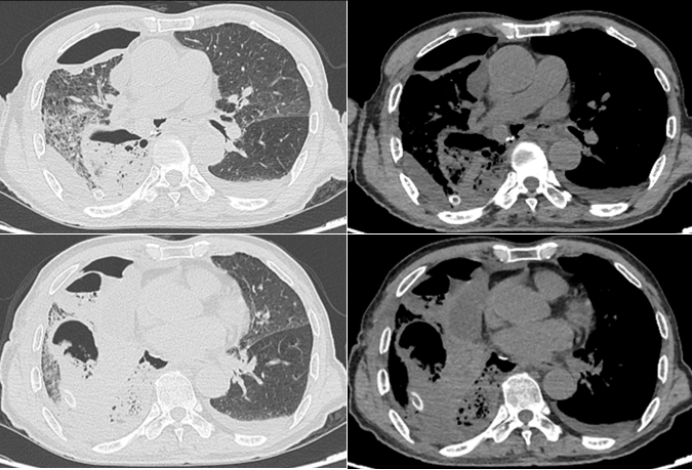

• 胸部CT(2025-02-28):双肺大量新发渗出,病灶主要集中在双下肺,大片实变,肺不张,少量胸腔积液(图9)

图片

9  患者胸部CT(2025-02-28)